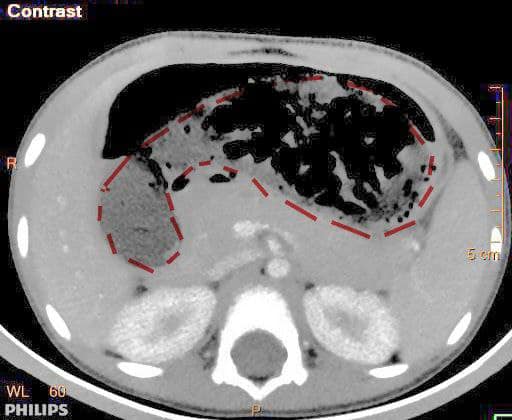

ក្នុងនោះ មានករណីក្មេងស្រីតូច អាយុ៥ឆ្នាំនេះ ចេះតែលួចញ៉ាំស្ករកៅស៊ូ មិនឲ្យម្តាយដឹងរាប់ខែមកហើយ ព្រោះថាផ្អែមឆ្ងាញ់ ដោយម្តាយជាអ្នកលក់ចាប់ហ៊ួយនិងស្ករកៅស៊ូនោះផង ដុំស្ករកៅស៊ូ ដែលនាងលេបចូល បន្តិចម្តងៗ ជាច្រើនខែឆ្នាំ បង្កើតបានជាដុំកៅស៊ូមួយយ៉ាងធំស្ទើរប៉ុនទំហំក្រពះ ធ្វើឲ្យស្ទះក្រពះនិងពោះវៀន នាងត្រូវបានក្រុមគ្រូពេទ្យគន្ធបុប្ផា ជួយសង្រ្គោះជីវិត ដោយឆ្លុះថតក្រពះ និងទីបំផុតត្រូវវះកាត់ក្រពះពោះវៀន ដល់ទៅ២លើក ទើបយកដុំស្ករកៅស៊ូនោះបាន។ អរគុណគន្ធបុប្ផា រាល់ការព្យាបាល ទាំងអស់ គឺឥតគិតថ្លៃ សម្រាប់គ្រប់ៗគ្នា ដោយគ្មានការរើសអើង អរគុណមូលនិធិគន្ធបុប្ផាស្វីស និងមូលនិធិគន្ធបុប្ផាកម្ពុជា អរគុណចំពោះសប្បុរសជនគ្រប់ៗរូប ដែលតែងតែគាំទ្រដល់ដំណើរការមន្ទីរពេទ្យគន្ធបុប្ផា ៕ »